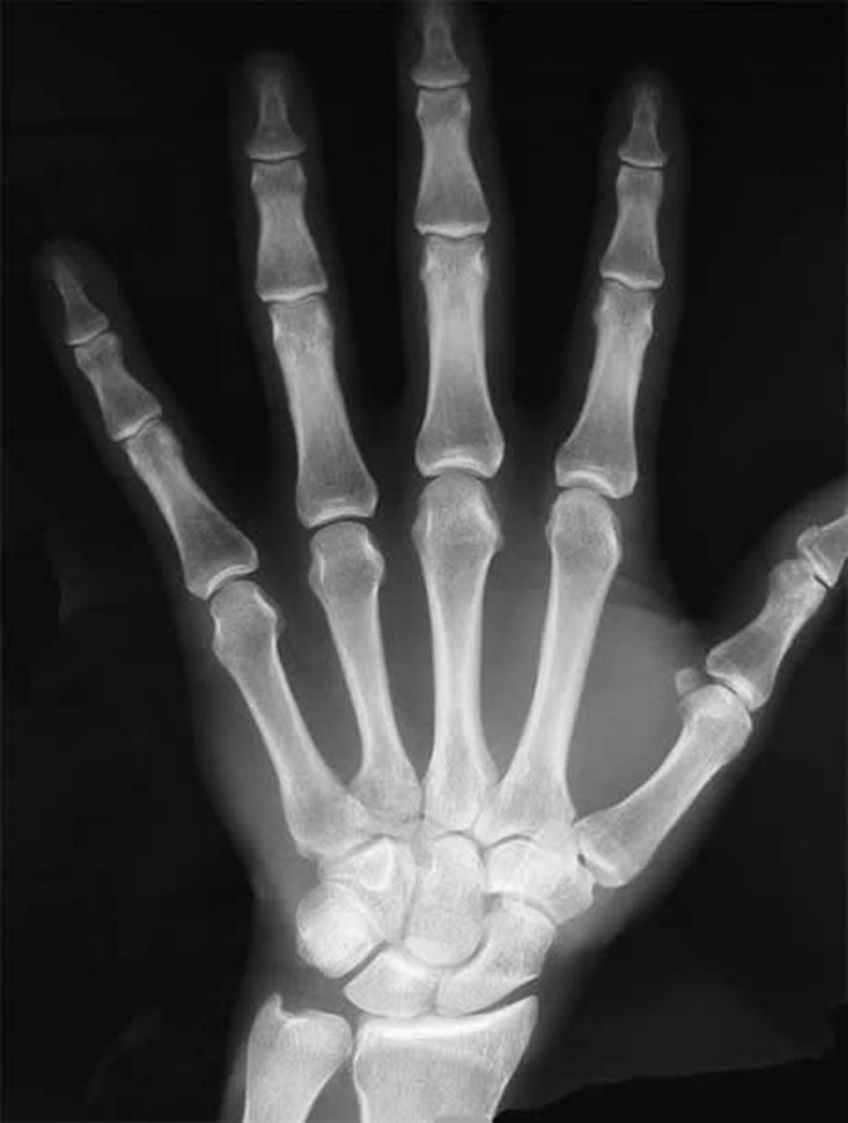

What view is this

PA wrist

What is 1

capitate

What is 16

trapezoid

What is 15

trapezium

What is 12

scaphoid

what is 6

lunate

what is 17

triquetrum

what is 8

pisiform

what is 18

ulna

what is 10

radius

what is 4

hamate